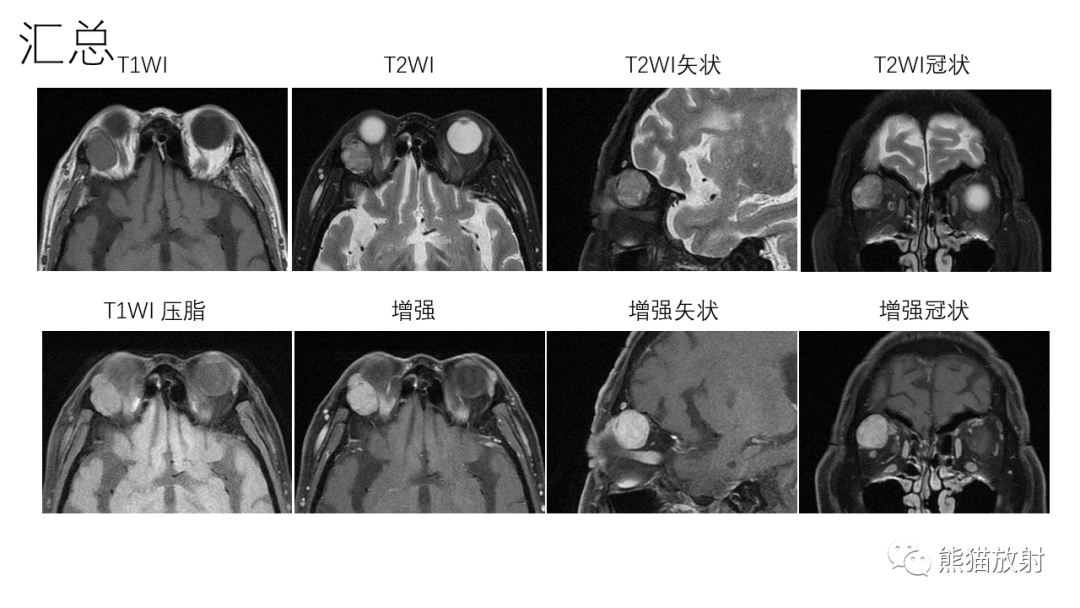

【PPT】泪腺多形性腺瘤 VS 眼眶淋巴瘤-8

【PPT】泪腺多形性腺瘤 VS 眼眶淋巴瘤-9